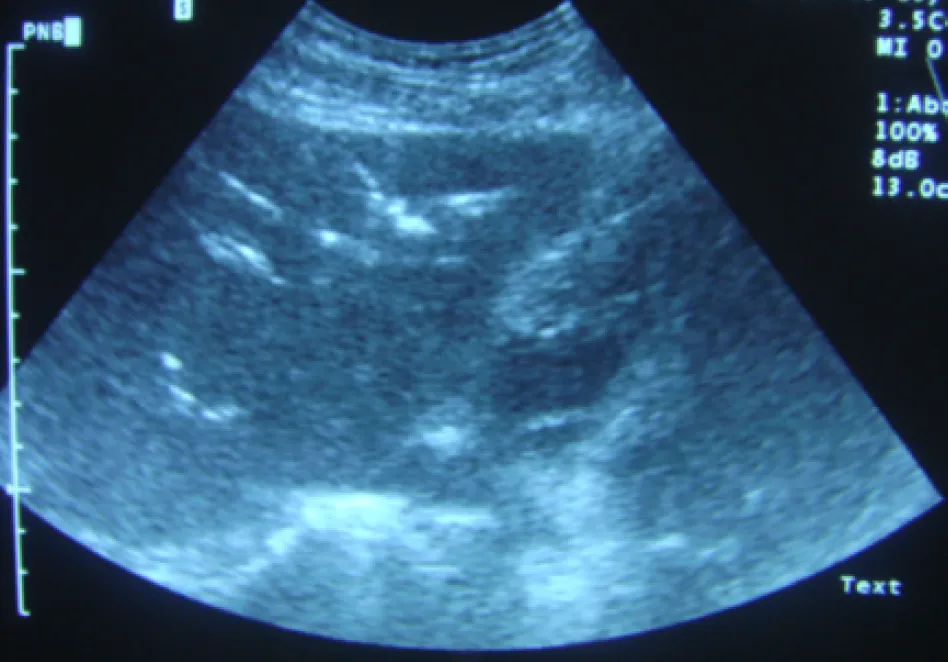

【112-2 醫學(三) 第75題】下圖為肝臟超音波掃描,最可能的診斷為:

這張肝臟超音波影像的關鍵在於肝內膽管系統中出現了高迴音性的亮點,並且伴隨著典型的「髒陰影 (dirty shadowing)」或「迴響假影 (reverberation artifact)」,這是膽道系統內有氣體的明確證據。